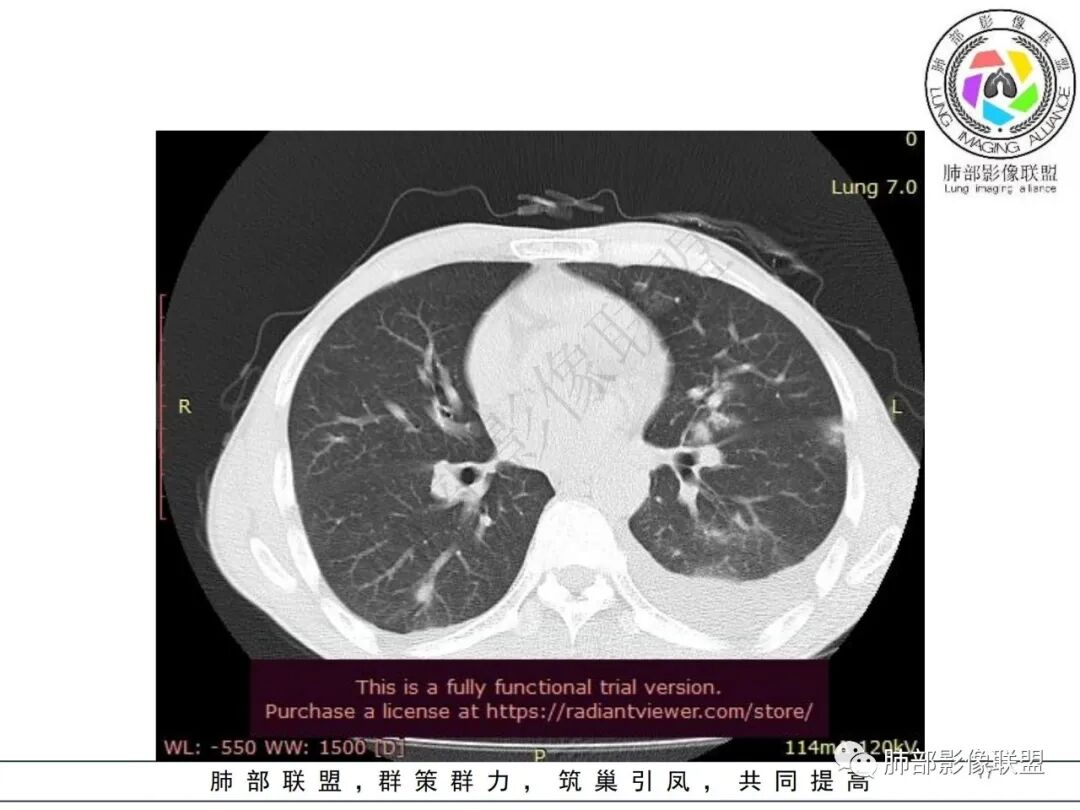

双肺多发大小不等结节影,边缘伴有磨玻璃影,边界欠清,部分与血管束相连,支气管似有穿行病灶内,结节有融合,左肺下叶厚壁空洞,伴有反晕征,左侧胸水,临床中年男性,发热40℃,CRP增高,感染性病变,1:类鼻疽伯克霍尔德菌(好发海南,影像表现也符合)

影像:双肺多发结节、实变影,大部分病灶边界不清,分布相对随机,左下肺坏死空洞形成,伴左侧胸水。

影像表现:双肺弥漫分布斑片影、实变影、磨玻璃影、结节影,晕征、反晕征,随机分布,部分病灶空洞形成前兆,左侧胸腔积液。

两肺多发斑片状实变影,周围GGO

主体还是沿支气管,大片叶段性分布

影像表现:双肺多发结节、实变影,大部分病灶边界不清,随机分布趋势,左下肺“反晕征”,似有形成空洞趋势。左侧胸腔积液。治疗后复查 ,大部分病灶吸收好转,呈较为典型血播分布,肝脏低密度块影,边界不清,符合肝脓肿。